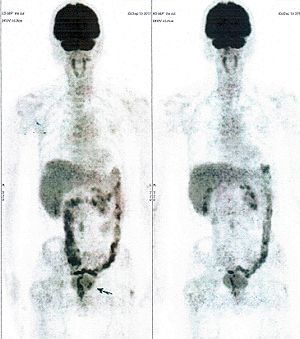

Below are some of the cases, from more than 80 cases we have treated so far with good results. When reading the PET/CT scans, the picture on the left is before treatment, and the picture on the right is after treatment. The intensity of black represents the activity of the cancer, but some black areas are not cancer: brain, heart, radioactive urine in bladder. For the heart, the intensity of black depends on the number of hours of fasting: if more than 10 hours, the heart is not even black, but if fasting is less than 6 hours, it is very black. The intensity of black in the brain can be variable in different scans depending on the brain activity at the time of the scan. The intensity of black in the radioactive urine can also be variable due to the hydration of patients and the time of injection of diuretic.

CASE NO: 3 (PROSTATE CANCER)

A middle-aged man with castration resistant prostate cancer, having failed all currently available cancer treatment, was very weak, and getting worse every day. The PET/CT scan showed he had massive bone metastases. After a few treatment, all the bone metastases went into remission. About 6 months later, he is still in remission.

CASE NO: 4 (PROSTATE CANCER)

A middle-aged man with castration resistant prostate cancer and massive bone metastases, failed all currently available cancer treatment, including with the new and expensive drug XTANDI. After a few treatment, most of the bone metastases went into remission, and the remaining ones are less active. Treatment will continue. Cases no: 3 and 4 show that terminal prostate cancer today can be cured with our new cancer treatment.